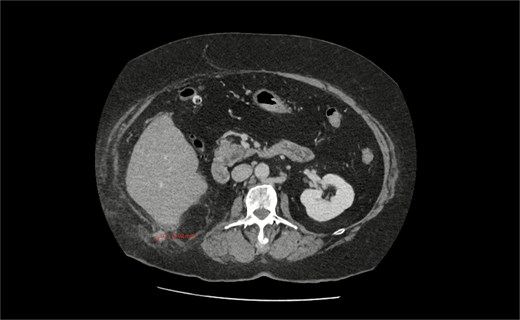

An urgent computed tomography (CT)-abdomen/pelvis highlighted an inflamed appendix extending into a small hernial defect in the right posterolateral abdominal wall (Figs 1–3). Thus, diagnosing retroperitoneal acute appendicitis within a right nephrectomy incisional hernia. The patient was started on intravenous Ceftriaxone and Metronidazole prior to deciding upon an open appendicectomy and repair of the incisional hernia using biological mesh.

CT axial section showing a pathologically thickened appendix of 12 mm diameter (red measurement) projecting through a right posterolateral abdominal wall defect. There is also notable inflammatory fat stranding, with no evidence of perforation.